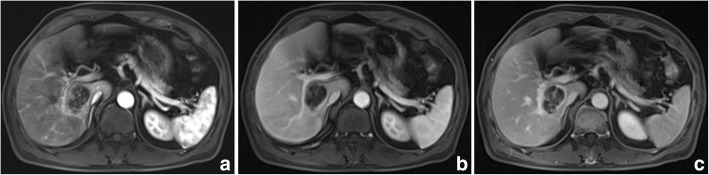

Fig. 4.

Sarcomatous hepatocellular carcinoma in a 55 year-old man. The mass shows a mix rim and internal enhancement in the arterial phase (a) and progressive or persistent enhancement on the portal venous and equilibrium phase (b, c). An incomplete capsule is found (c)

The imaging features of PHSC are summarized in Table 3. All of the tumors were located near the liver subcapsular area (Figs. 1, 2, 3, 4, 5, 6 and 7), with an obvious dominance (90%) in the right lobe. Tumors ranged in diameter from 3.4 cm to 22.0 cm with a mean diameter of 8.3 cm. The most common gross morphology was massive (six cases) with round or oval shapes, and the remaining included nodular (two cases), infiltrative (one case) (Fig. 5), and multinodular confluent patterns (one case) (Fig. 6). Six tumors were poorly defined, especially at CT (five cases) and the rest were demarcated at MRI. The density or signal of the tumors was mainly heterogeneous (eight cases) for hemorrhage or necrosis. The hemorrhage was found in 1S-HCC and 2 S-ICCs, with one S-ICC rupturing into the subcapsular space as shown on MR imaging (Fig. 2). Five complete or partial capsules (Figs. 2 and 4) were found on CT (one case) or MRI (four cases) and two of them were pathologically confirmed in the S-ICC and S-HCC–CC.

Regarding the distribution of enhancement, peripheral enhancement was seen in 2 S-ICCs and 3 S-HCCs (Fig. 3). Mix rim and internal heterogeneous enhancement (Fig. 4) was found in 2 S-HCCs, internal heterogeneous enhancement was shown in 2S-HCCs and 1 S-HCC–CC (Fig. 6), and no homogeneous pattern was observed. Eight tumors including 2 S-ICCs, 5 S-HCCs and 1 S-HCC–CC were hypo-vascular (Figs. 1, 2, 3 and 4) and the remaining 2 S-HCCs mainly presented hyper-intense enhancement on the arterial phase. As to the enhancement degree of the solid part in the tumor, six tumors showed hyper enhancement compared to the background liver.

With respect to the dynamic pattern of enhancement, of the ten tumors, 40% with 2 S-HCCs and 2 S-ICCs showed peripheral enhancement on the arterial phase and progressive enhancement towards the center (Fig. 2) on the later phases, 20% with 2 S-HCCs showed heterogeneous enhancement on the arterial phase and progressive or persistent enhancement on the later phase (Figs. 2, 3, 4 and 5), and 30% with 3 S-HCCs presented obvious peripheral and heterogeneous enhancement on the arterial phase and then wash out peripherally and partially on the later phase, mimicking ordinary HCC. The remaining S-HCC–CC exhibited a variable enhancement character for its multinodular change (Fig. 6). The tumor showed mild inhomogeneous enhancement on the arterial phase, and the portion near the subcapsular area of the tumor showed persistent thin rim enhancement accompanied by an mural nodular on the portal and equilibrium phase, next to the cyst change was the mild to moderate progressive fill-in enhancement, and the upper portion presented washout on the equilibrium phase.

On the MR imaging of five patients, bright signal intensity similar to that of cyst or hemangioma on T2WI might be explained by necrosis [14] and the signal might be attributed to hemorrhage seen as hypointensity or hyperintensity on T1WI and hypointensity on T2WI not only inside the center of the tumor but also in the subcapsular area. The other S-HCCs showed inhomogeneous high signals on DWI and T2WI, similar to the “normal” type. Five tumor capsules were observed on imaging, and only two of them were confirmed in pathology. It was reported that a high incidence was correlated with well differentiated HCC and the tumor capsules were much more common in ordinary HCC when compared with the S-HCC [5]. Similar to the result, we did not find capsules in S-HCCs, except for a complete capsule in the S-ICC and a partial one in the S-HCC-CC pathologically.